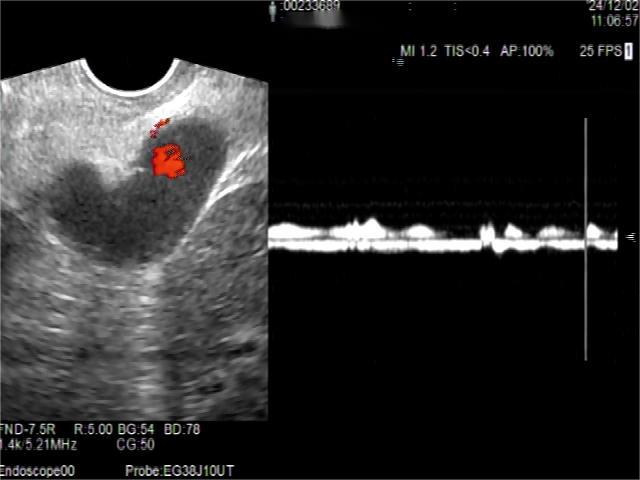

• 超声内镜引导下胃旁曲张静脉精准断流术治疗食管胃静脉曲张出血的疗效分析(附20例报告)

2025, 31(8):85-90. DOI: 10.12235/E20250036

摘要 (153) HTML (42) PDF 5.38 M (98) 评论 (0) 收藏

摘要:目的 探讨超声内镜引导下胃旁曲张静脉精准断流术治疗食管胃静脉曲张出血的疗效。方法 回顾性分析2024年1月1日-2024年12月31日于该院接受超声内镜引导下胃旁曲张静脉精准断流术治疗的20例肝硬化食管胃静脉曲张出血患者的临床资料,并评估治疗效果。结果 20例患者均顺利完成超声内镜引导下胃旁曲张静脉精准断流术;注射组织胶联合置入弹簧圈(16例)和单独注射组织胶(4例)均成功阻断胃旁来源的曲张静脉;所有患者均未发生穿孔、食管贲门狭窄、大出血、败血症和异位栓塞。1例单独注射组织胶的患者,术后胃旁曲张静脉少许渗血,经降低门静脉压力治疗3 d后好转,另1例单独注射组织胶患者,术后出现低热,抗感染3 d后体温恢复正常。结论 超声内镜引导下胃旁曲张静脉精准断流术治疗食管胃静脉曲张出血的临床疗效好,异位栓塞、大出血、感染和穿孔等并发症少,但仍需要密切随访,观察胃旁曲张静脉的排胶问题。